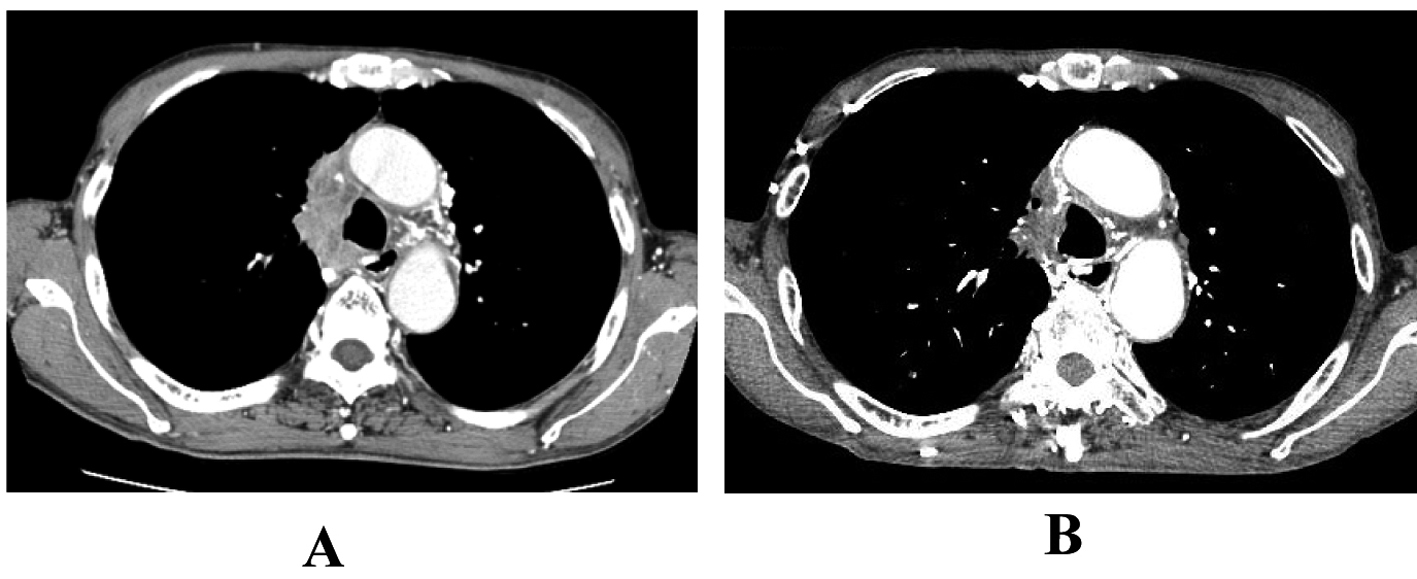

A 65-year-old man was admitted to our hospital because of face edema, general fatigue and appetite loss in July 2002. Chest X-ray and chest CT scan revealed an anterior mediastinal mass (Fig. 3A). After histological diagnosis of thymic carcinoma (squamous cell carcinoma) by percutaneous CT-guided biopsy, he was treated with 5 cycles of ADOC chemotherapy. Good partial response was observed (Fig. 3B). In April 2011, he presented supra vena cava syndrome again. CT scan indicated a mediastinal mass (Fig. 4A). Bronchoscopic examination was performed and transbronchial needle biopsy revealed recurrence of thymic cancer. Readministration of ADOC was initiated in August 2011. After one cycle of ADOC chemotherapy, chest CT scan revealed a partial response (Fig. 4B). However, the patient developed febrile neutropenia and bacterial pneumonia during the first cycle of chemotherapy. He refused subsequent chemotherapy and is currently under observation without symptoms.

![]() Click for large image | Figure 4. The response to second-line ADOC chemotherapy in case 2. Chest computed tomography before second-line ADOC chemotherapy (A) and after a cycle of second-line ADOC chemotherapy (B). |